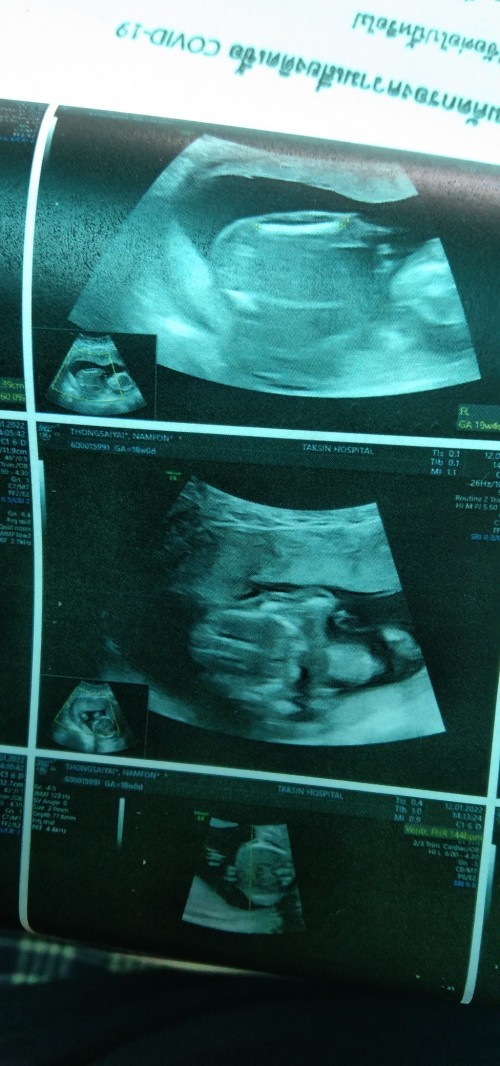

18 w จ้า #เพศชาย #ทีมมิ.ย

Post reply image